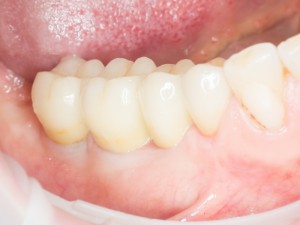

Но это еще не самое веселое. Допустим, мы решили проблему соединения «имплант-абатмент», у нас нет проблем с люфтами, а сам имплантат настолько хорошо интегрировался, что способен любую нагрузку в любом направлении. Возникает другая проблема — размер супраструктуры и соответствие ее нормальной биологической длине коронки зуба:

На фотографии выше, коронки опираются на обычные импланты, но даже в этом случае увеличение высоты супраструктуры усложняет гигиену и требует более пристального дальнейшего наблюдения. С ультракороткими имплантами, если честно, всё еще хуже.

Как будет выглядеть такая конструкция? Какой длины будут коронки? Возможно, на эстетику даже можно забить, ведь для некоторых людей красота зубов в боковом сегменте челюсти за пределами эстетически значимой зоны не так важна, но… как быть с уходом за протетической конструкцией и ежедневной гигиеной? Ведь, чем больше по размеру протез, тем сложнее за ним ухаживать. Тем больше мест, где может остаться зубной налет, а это, как вы понимаете, может привести к очень неприятным последствиям — периимплантиту, что для ультракоротких имплантов очень критично. А застревание пищи между протезом и десной? Можно ли назвать это «повышением качества жизни пациента»? Вряд ли.